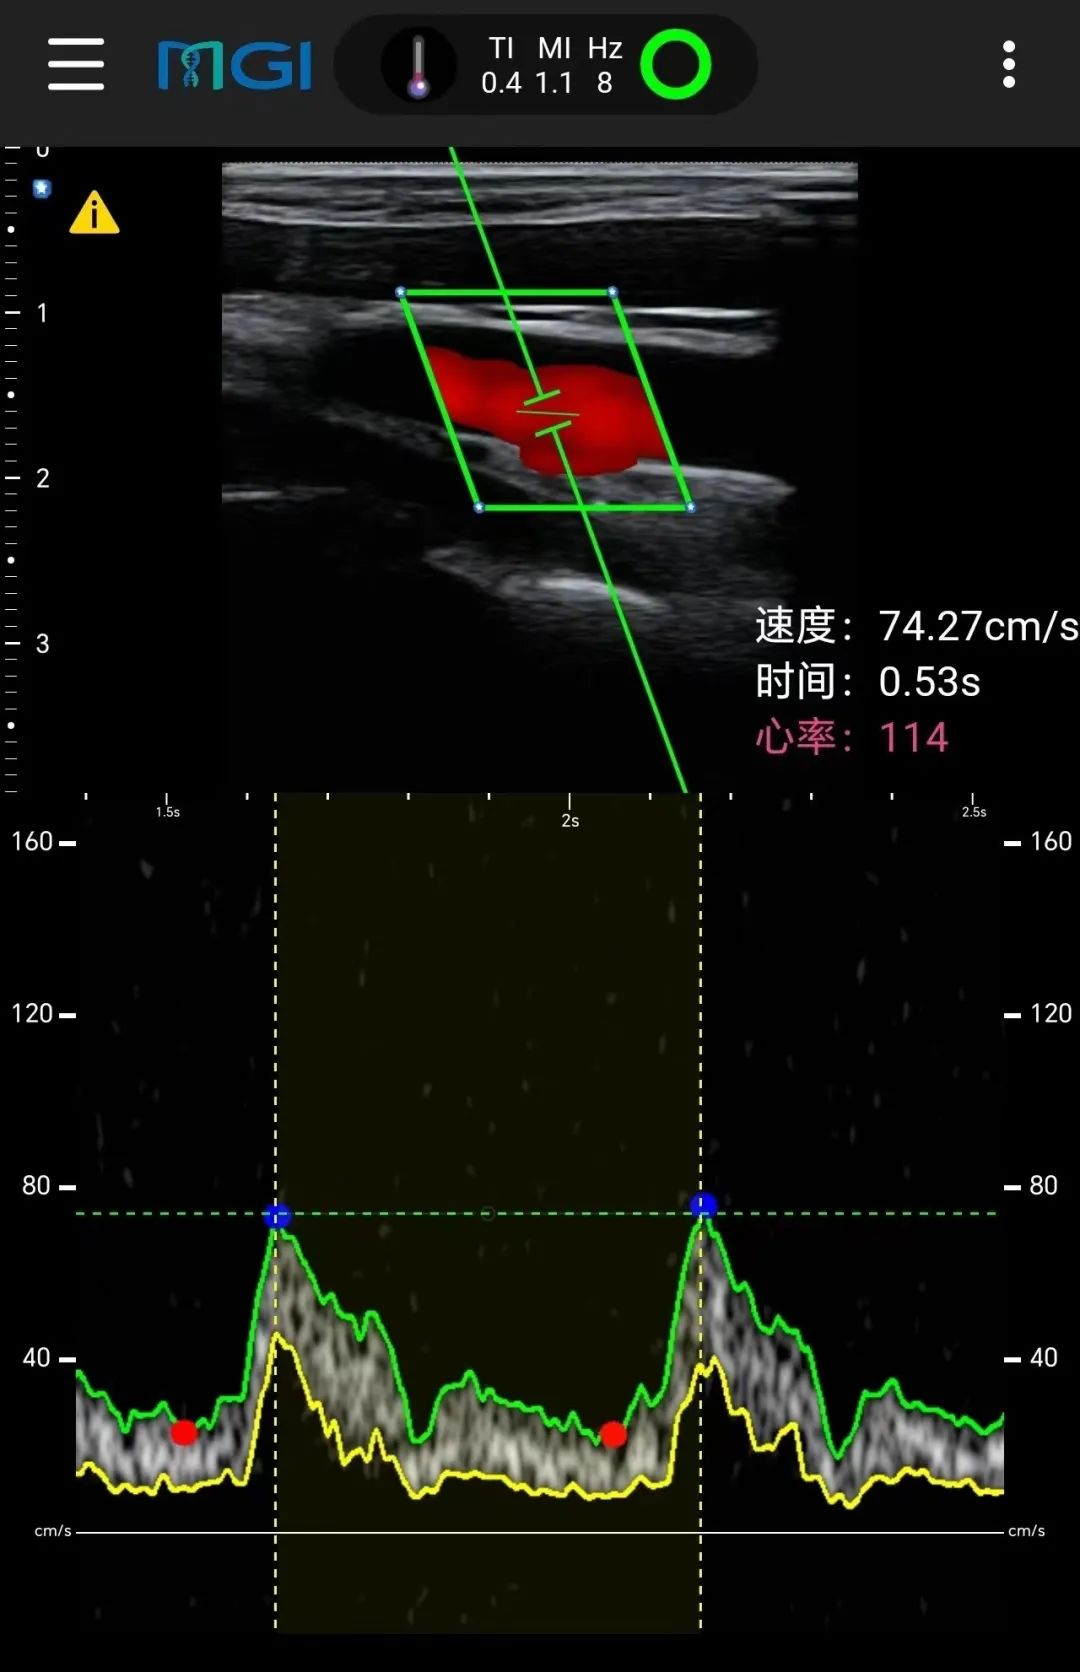

5月21日10时28分,华大集团联合创始人、董事长汪建带领华大登山队从北坡成功登顶珠穆朗玛峰,并传回了全球首份来自世界之巅的超声图与脑电数据。这也是70岁的汪建第二次登顶珠峰,刷新了中国登顶珠峰最年长纪录。  汪建(中)带队成功登顶珠峰本次攀登珠峰以科学探索为目的,旨在开创性产出高海拔科研数据,深入解析人体在极高海拔地区的适应性生理机制,为未来的科学和产业发展带来新的突破和启发。今年4月18日,华大登山队抵达日喀则珠峰大本营,正式开启本次珠峰科研计划。在高原适应性训练和攀登过程中,华大登山队员持续监测和采集了从0米到8848米不同海拔高度下核心队员的生理指标、脑认知、眼动、眼底、运动机能、心肺超声等多维表型数据,获得了基因组、蛋白组、代谢组、影像组及细胞组等多组学数据。依托华大自主研发的核心工具,以及在脑科学、眼科学、高原医学、运动医学等领域已取得的成果,华大将利用本次科研计划获得的数据,来助力构建高原人体健康生命大模型。据汪建介绍:“2010年,我们基于生命中心法则,发现了高原适应性基因EPAS1;这一次,我们转向了时空法则,希望能从时间与空间维度,进一步深化对遗传与环境协同作用的理解。”2010年7月2日,华大科研团队揭示了人类适应高原环境的秘密——EPAS1基因突变,相关研究在《科学》杂志发表 为更好地完成本次珠峰科研计划,华大在海拔5200米的“珠峰实验室”部署了一系列自主研发的“黑科技”,及时响应检测需求与科研任务。 华大智造基因测序仪DNBSEQ-G99、DNBSEQ-E25以及无线掌上超声等多款“硬核”设备均在“珠峰实验室”完成了高海拔性能验证,各项数据指标表现良好,刷新了最高海拔运行纪录。这也表明,这些设备未来可为高海拔等极端环境下的多组学研究提供有力工具支撑,助力高原环境监测和高原医学发展。“珠峰实验室”部署了一系列华大自主研发的“黑科技”其中,华大智造无线掌上超声自带远程会诊功能。在海拔8300米的营地,华大登山队员使用该设备完成了与远在4000公里外的北京医院超声科主任、2500公里外的四川阿坝临床医生以及4000公里外的深圳团队的连线,成功实现会诊,并对登山队员进行了颈动脉实时超声扫查,以探索颈动脉血流动力学在极端高海拔地区的影响。 值得一提的是,华大智造无线掌上超声还随队登顶珠峰,在峰顶实时获取了登顶队员的颈动脉超声扫查图像,这也是全球首张诞生于世界之巅的超声图。同样令人振奋的是,本次在世界之巅首次被记录下来的,还有登山队员的静息态脑电数据。

在珠峰顶实时获取的颈动脉超声扫查图像 1975年5月,全球首位从北坡登顶珠峰的女登山家潘多,从峰顶传回世界上第一份心电遥测图。近50年后的今天,华大登山队从峰顶传回了第一份超声图和脑电数据,希望以更多维度的数据,探究人在高原适应过程和极限攀登前后的生理状态变化。在南极、北极之外,青藏高原与马里亚纳海沟分别被称为地球“第三极”和“第四极”。贯穿地球三四极的科学探索,将有助于回答有关生命起源和极端环境适应的科学问题。